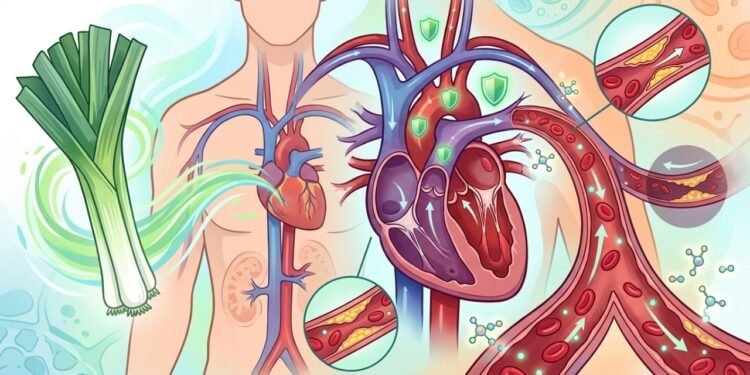

Um vegetal de sabor tão suave e adocicado, que quase sempre aparece como coadjuvante na sopa, pode ser o aliado mais discreto do seu sistema vascular. A ciência mostra que o consumo de alho-poró no coração vai muito além de um simples hábito culinário: ele aciona compostos sulfurados e flavonoides que trabalham em várias frentes para manter as artérias desobstruídas e o sangue fluindo com menos resistência.

O principal mecanismo envolve a produção de óxido nítrico, uma molécula que sinaliza para as paredes das artérias relaxarem. Um estudo publicado no SciELO mostrou que o extrato alcoólico de alho-poró aumentou significativamente o óxido nítrico sérico em ratos hipertensos.

Paralelamente, flavonoides como o kaempferol inibem a expressão de mediadores inflamatórios que enrijecem a camada interna dos vasos. Com menos inflamação, o endotélio mantém sua flexibilidade natural.

Um experimento com coelhos hipercolesterolêmicos, indexado no PubMed, administrou extrato de alho-poró em doses crescentes por 12 semanas. O resultado foi uma queda dose-dependente do colesterol total e uma redução significativa do LDL.

O vegetal ataca várias frentes da síndrome metabólica. As fibras prebióticas, especialmente a inulina, melhoram a sensibilidade à insulina e ajudam a evitar os picos de glicose que intoxicam os vasos sanguíneos ao longo do tempo.

- Colesterol LDL elevado: os compostos sulfurados reduzem a oxidação das partículas de LDL.

- Hipertensão arterial: o efeito vasodilatador e diurético ajuda a baixar os níveis pressóricos.

- Inflamação crônica: o kaempferol bloqueia vias inflamatórias que danificam as artérias.

- Estresse oxidativo: os antioxidantes neutralizam radicais livres antes que lesem o endotélio.